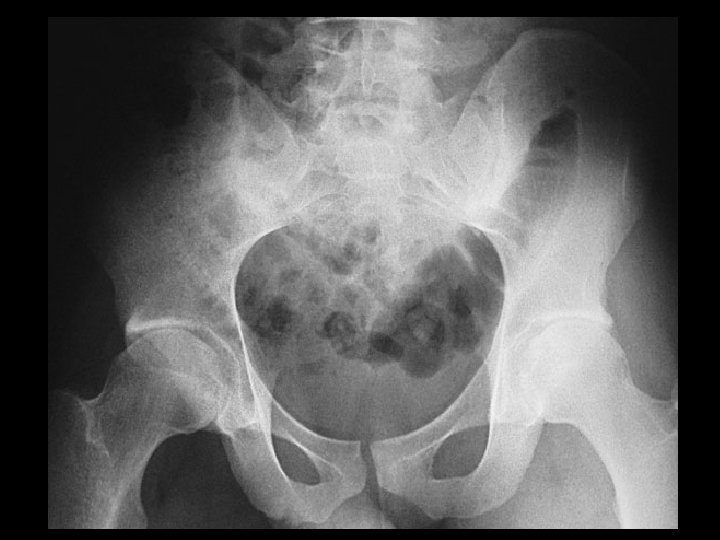

Paget’s disease • Findings: – trabecular and cortical thickening involving the left hemipelvis and proximal femur • ddx: – slcerotic mets (unlikely)